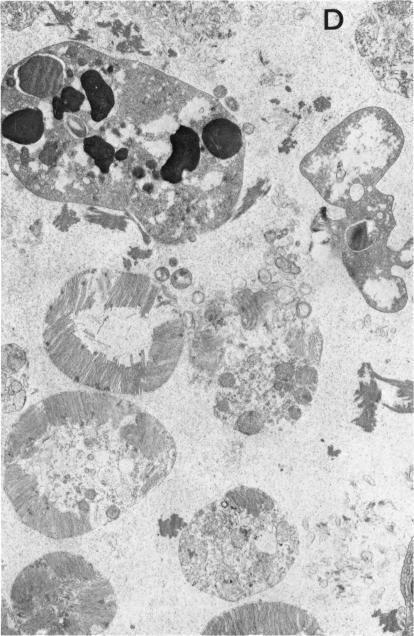

It is known that the visual loss in severe uveitis is due primarily to retinal tissue damage. In order to test the hypothesis that this damage may result from oxygen free radical-induced peroxidation of retinal membrane lipids, the generation of oxygen metabolites at the site of intraocular inflammation was investigated in an animal model of uveitis induced by retinal S-antigen. The effect of these metabolites on the initiation of retinal damage was characterized by histochemical, biochemical, morphologic, and morphometric methods. Light and electron microscopic studies at the early stage of the inflammation disclosed disorganization, degeneration, and necrosis of the photoreceptors and other retinal cells. Novel histochemical procedures demonstrated formation of superoxide and hydrogen peroxide at the site of uveoretinitis. Chemiluminescence measurements on uveoretinal tissue from these experimental animals revealed generation of superoxide anion and hydroxyl radicals. During the early phase of the uveoretinitis, concomitant with generation of the oxygen metabolites, there was peroxidation of retinal membrane lipids. The peroxidation products consisted of CD, MDA, hydroperoxides, and others. Associated with these changes was a selective depletion of the PUFA 22:6, decrease of which in the retinal composition has been shown to affect visual function. The morphologic and biochemical investigations clearly indicate that oxygen free radicals are generated at the site of uveoretinitis and that the retinal damage is mediated by peroxidation of lipids that are present in the retinal cell membranes. It would thus seem logical that such intraocular inflammation and the resultant retinal damage could be suppressed by antioxidant enzymes and oxygen free radical scavengers. These studies provide for the first time clear indication for developing new therapeutic agents that possess oxygen free radical scavenging properties, for treatment of human uveitis.

已知严重葡萄膜炎导致的视力丧失主要是由于视网膜组织损伤。为了验证这种损伤可能是由氧自由基诱导的视网膜膜脂质过氧化所致的假说,在视网膜S抗原诱导的葡萄膜炎动物模型中,研究了眼内炎症部位氧代谢产物的产生情况。通过组织化学、生物化学、形态学和形态计量学方法,对这些代谢产物对视网膜损伤起始的影响进行了表征。炎症早期的光镜和电镜研究显示,光感受器和其他视网膜细胞出现紊乱、变性和坏死。新的组织化学方法证明,葡萄膜视网膜炎部位形成了超氧化物和过氧化氢。对这些实验动物的葡萄膜视网膜组织进行化学发光测量,结果显示产生了超氧阴离子和羟基自由基。在葡萄膜视网膜炎的早期阶段,伴随着氧代谢产物的产生,视网膜膜脂质发生了过氧化。过氧化产物包括CD、丙二醛、氢过氧化物等。与这些变化相关的是多不饱和脂肪酸22:6的选择性消耗,视网膜成分中该脂肪酸的减少已被证明会影响视觉功能。形态学和生物化学研究清楚地表明,葡萄膜视网膜炎部位产生了氧自由基,视网膜损伤是由视网膜细胞膜中存在的脂质过氧化介导的。因此,通过抗氧化酶和氧自由基清除剂抑制这种眼内炎症及由此导致的视网膜损伤似乎是合乎逻辑的。这些研究首次为开发具有氧自由基清除特性的新型治疗药物以治疗人类葡萄膜炎提供了明确的依据。